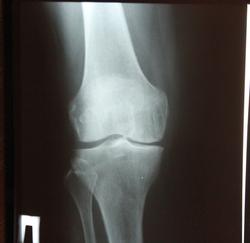

Тут, даже при желании, больше первой нарыть не возможно с учетом таких краеугольных признаков, как субхондральный склероз и краевое остеофитообразование.

Щель медиально узковата, в верхнем полюсе надколенника (у нас принято и его учитывать) - остеофит огромный. Но на полноценную 2 все это не тянет.

Для второй сужение должно быть более 50%